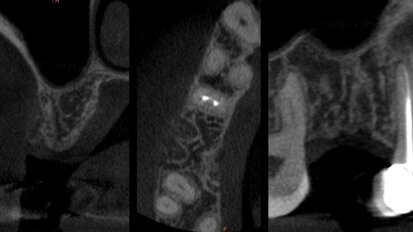

L’Intelligenza Artificiale e la Realtà Aumentata nella moderna pianificazione implantare: case report

Intelligenza Artificiale (“Artificial Intelligence”, AI) e Realtà Aumentata (“Augmented Reality”, AR) rappresentano la nuova frontiera nella ...